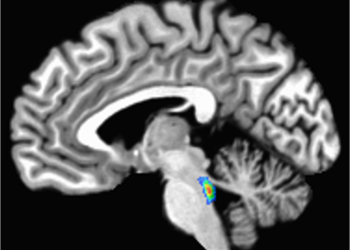

Virtually every living thing on Earth, from Patagonian penguins to newborn human babies, has been touched by the synthetic chemicals...